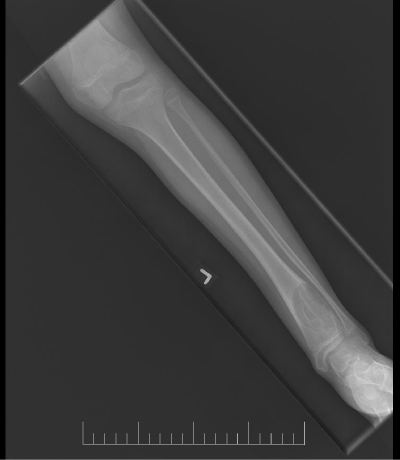

A 10-year-old female presented with left lower leg pain that had progressively increased over the duration of 1 year. On physical examination, tenderness was elicited on palpation of the distal tibia. Routine laboratory testing was normal. X-Ray was performed and revealed a lytic lesion with sclerotic margins in the left lower tibia (Figure 1). MRI was subsequently performed, demonstrating a left lower tibia lesion with low signal intensity on T1 weighted images (Figure 2), and high signal intensity on T2 weighted images (Figure 3). Pathology of the tumor revealed a diagnosis of a CMF. She was treated with curettage and autologous bone grafting (Figure 4). Post op eratively the left leg was immobilized with a plaster cast with restricted weight bearing (Figure 5). Follow up X-ray after 5 years demonstrates no tumor reoccurrence (Figure 6, Figure 7).

Figure 6: 5 year follow up AP X-ray of the left tibia/fibula.

Figure 7: 5 year follow up lateral X-ray of the left tibia/fibula.